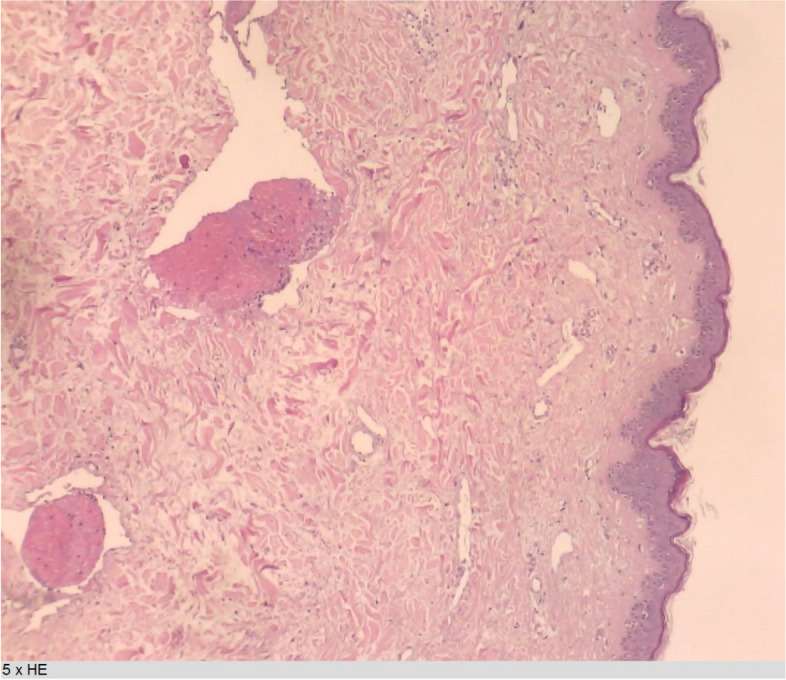

One week later, the blue color had largely changed to yellow (Fig. 2b). Red macula were visible. Gross telangiectasia was present around the boost area and in the inframammary fold. Their presence was known prior to this event. New full-thickness skin biopsies were performed, revealing a normal epidermis but dilated vessels and extravasation of red blood cells in the derm (Fig. 3). This led to the diagnosis of purpura. There were no signs of vasculitis. No tumor cells were observed. Manual lymphatic drainage of the breast was added to the treatment.

Fig. 3.

Light microscopy of derm with ectatic venules and intraluminal thrombi